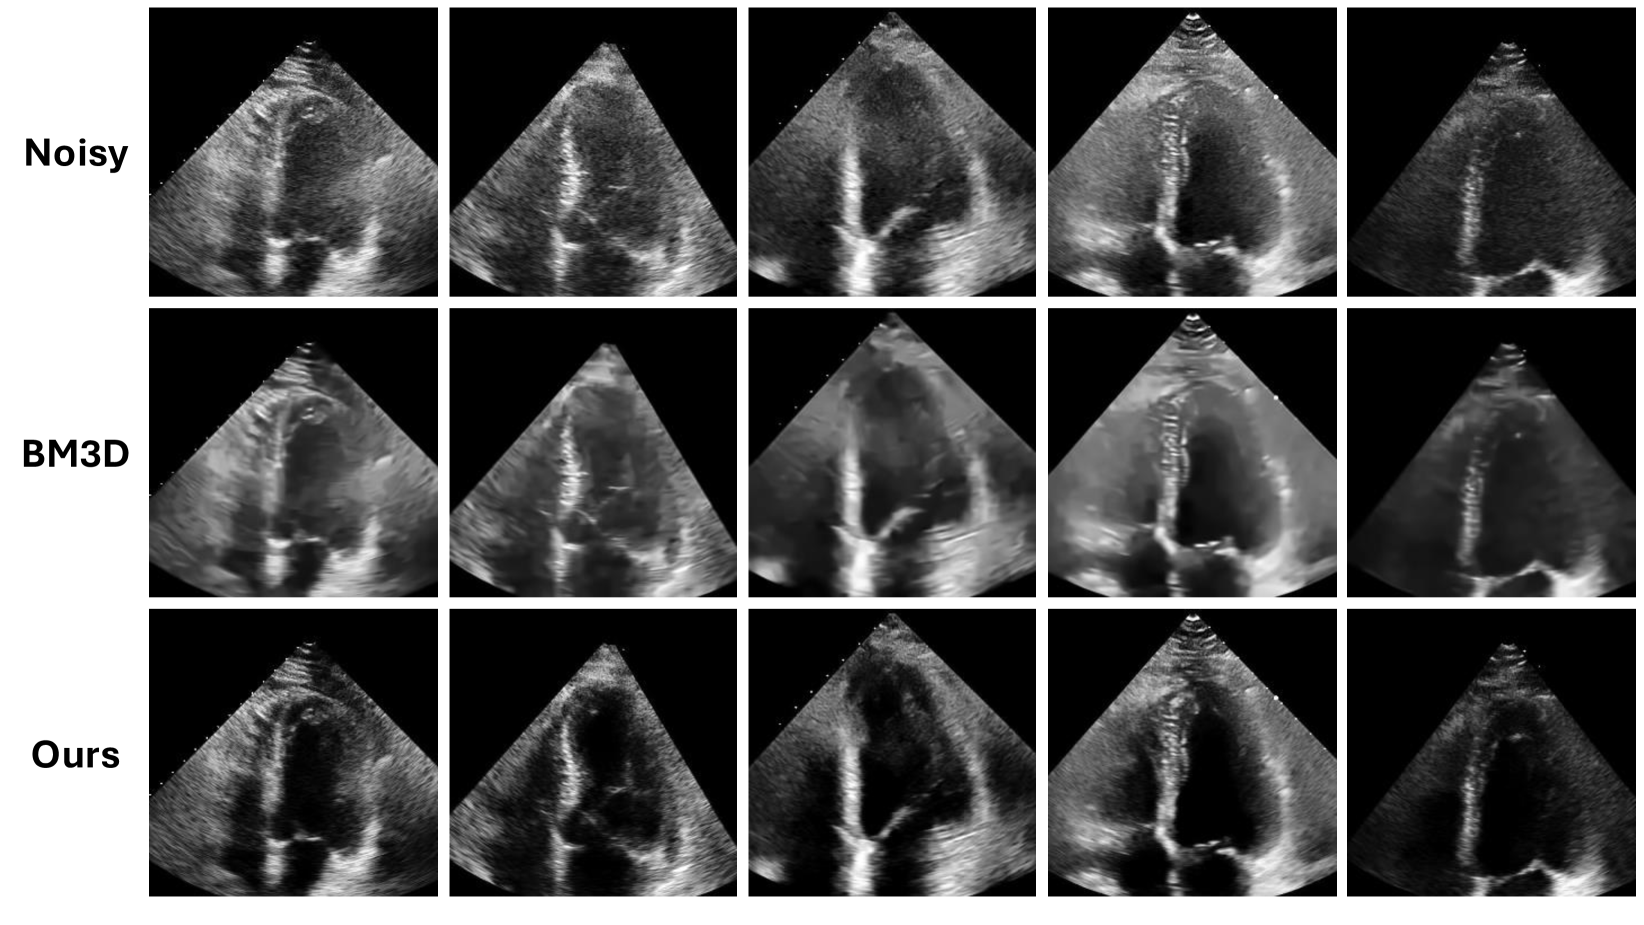

Figure 6: Qualitative results for internal set. Top row shows noisy images, middle row shows results from baseline BM3D method, and bottom row shows results from our method.

Refer to caption

Figure 7: Qualitative results for external set. Top row shows noisy images, middle row shows results from baseline BM3D method, and bottom row shows results from our method.

Furthermore, we provide qualitative comparisons in Fig. 6 and Fig. 7 and demonstrate their consistency with our reported quantitative findings. In both internal and external qualitative comparisons, a close examination of denoised images from BM3D shows that the algorithm compromises spatial resolution and fine textural details to smooth out high-frequency noise. Evidently, BM3D is incapable of removing noise in the atrial and ventricular chambers of depicted hearts in B-mode echo. By contrast, our method demonstrates the capability of removing noise in the cardiac chambers without compromising spatial resolution or fine textural detail. We highlight the notable difference in visual distinction between cardiac chambers and structures in the denoised images derived from our method in comparison to those resulting from BM3D.